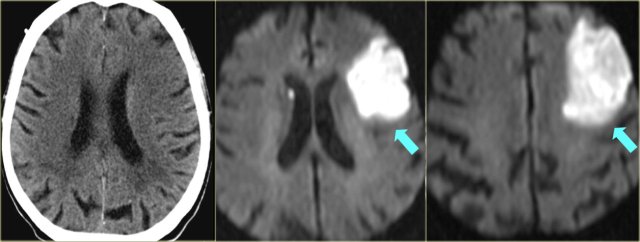

On the left another case.

The DWI and ADC map is shown.

Continue for the perfusion images

Now we can see that there is a severe mismatch.

Almost the whole left cerebral hemisphere is at risk due to hypoperfusion.

This patient is an ideal candidate for therapy.